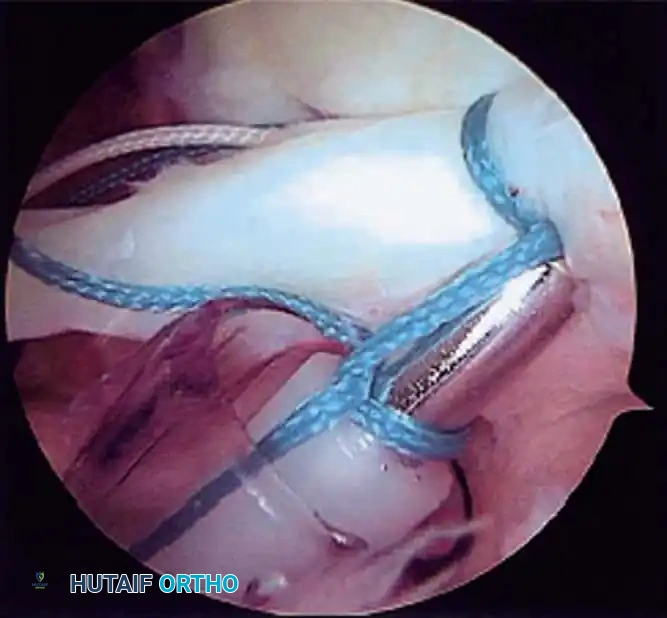

Once diagnostic evaluation is complete and hemostasis is secured, the therapeutic phase commences. Whether performing a SLAP repair, a Bankart stabilization, or a rotator cuff repair, the principles of tissue mobilization, anatomical footprint restoration, and secure biomechanical fixation remain paramount.

Modern arthroscopy relies heavily on suture anchors (biocomposite or all-suture constructs) and advanced arthroscopic knot-tying or knotless techniques. The ability to pass sutures through retracted, fibrotic tissue and secure them under appropriate tension without strangulating the microvascular supply is the hallmark of a master arthroscopist.